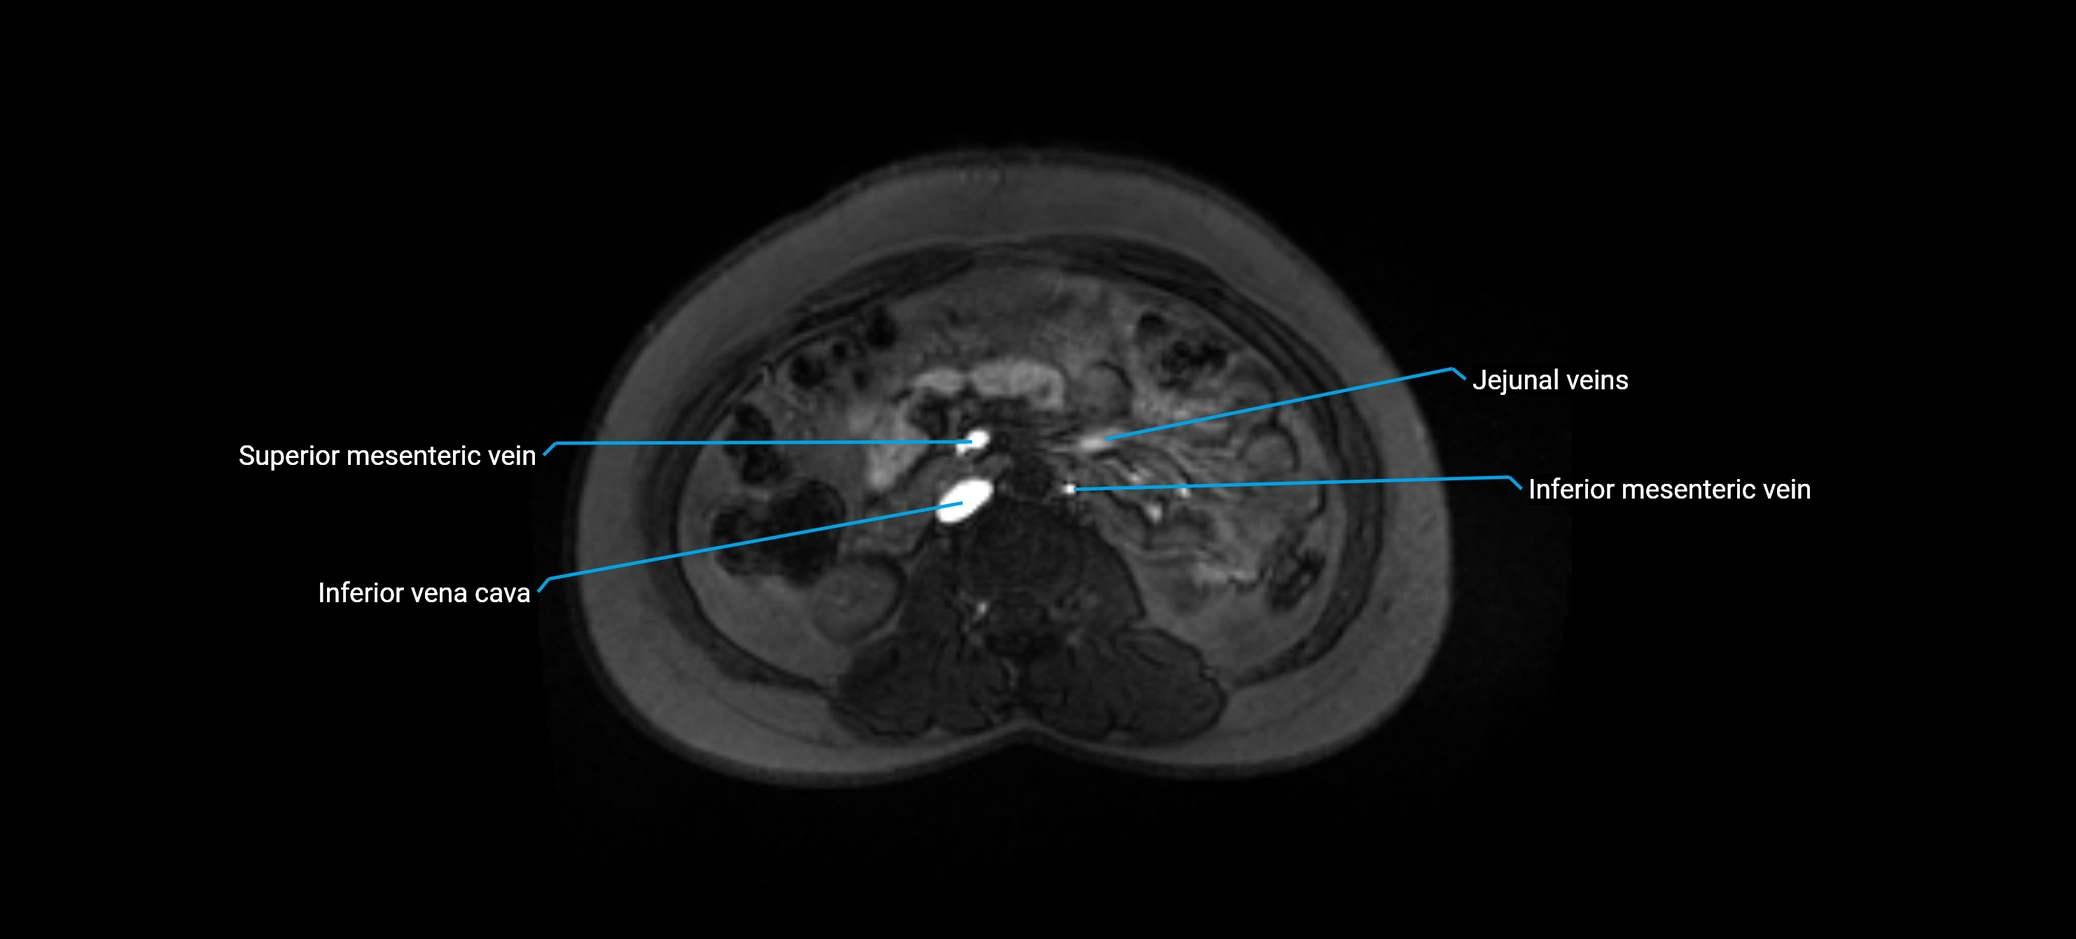

MRI image

image